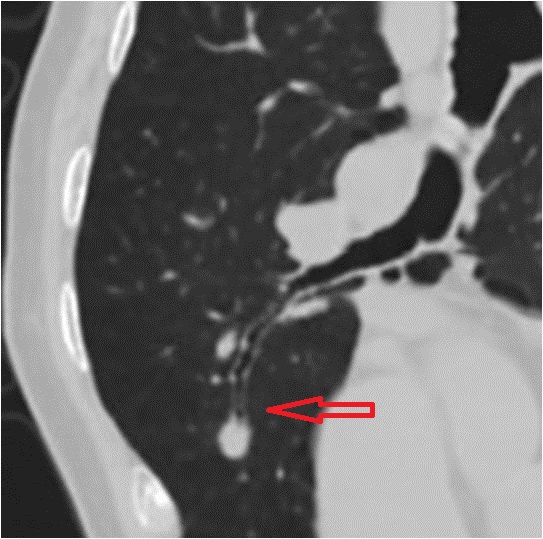

我们考虑到病灶位置特殊,给予患者俯卧位扫描(图7),让病灶更好的显示出来。

图7

在个性化扫描下取得优质容积数据,用薄层靶重建(图8)显示出病灶更多的细节,从图中可见,该结节存在分叶、毛刺、血管集束征、胸膜凹陷征等恶性结节常见征象。

图8

随后,用冠状位和矢状位显示病灶形态,用容积再现(VR)显示病灶表面情况(图9-12)。最后诊断:浸润性腺癌。